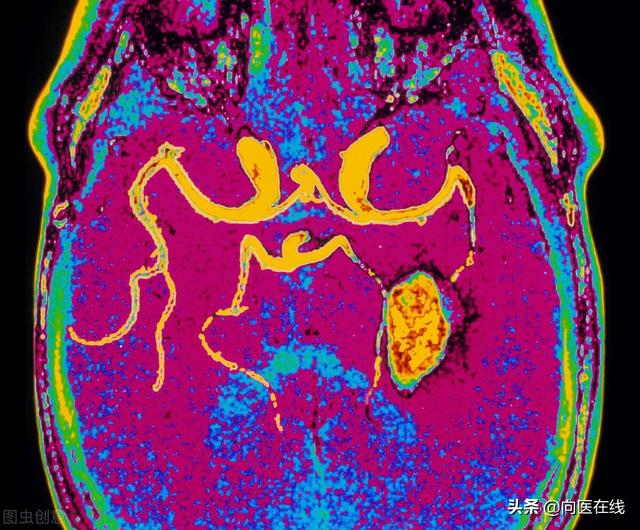

我们都知道它可以降血脂,这是对的。其原理主要是在降低胆固醇后防止脂质,并因血管壁沉积而引起动脉粥样硬化和动脉斑块的生长。因此,阿托伐他汀(他汀类药物)可以预防全身动脉粥样硬化。包括下肢动脉粥样硬化、颈动脉粥样硬化、冠状动脉粥样硬化和脑血管动脉粥样硬化,从而预防心梗、脑中风等心脑血管疾病。

引起心脑血管疾病的主要原因之一是炎症反应,引起血管内皮损伤和更多的血管斑块。一旦不稳定斑块破裂,就会形成血栓,进而引发心梗、脑梗等疾病。阿托伐他汀可以通过抗炎和稳定斑块来控制心脑血管疾病,预防冠心病、心肌梗死和脑梗死。